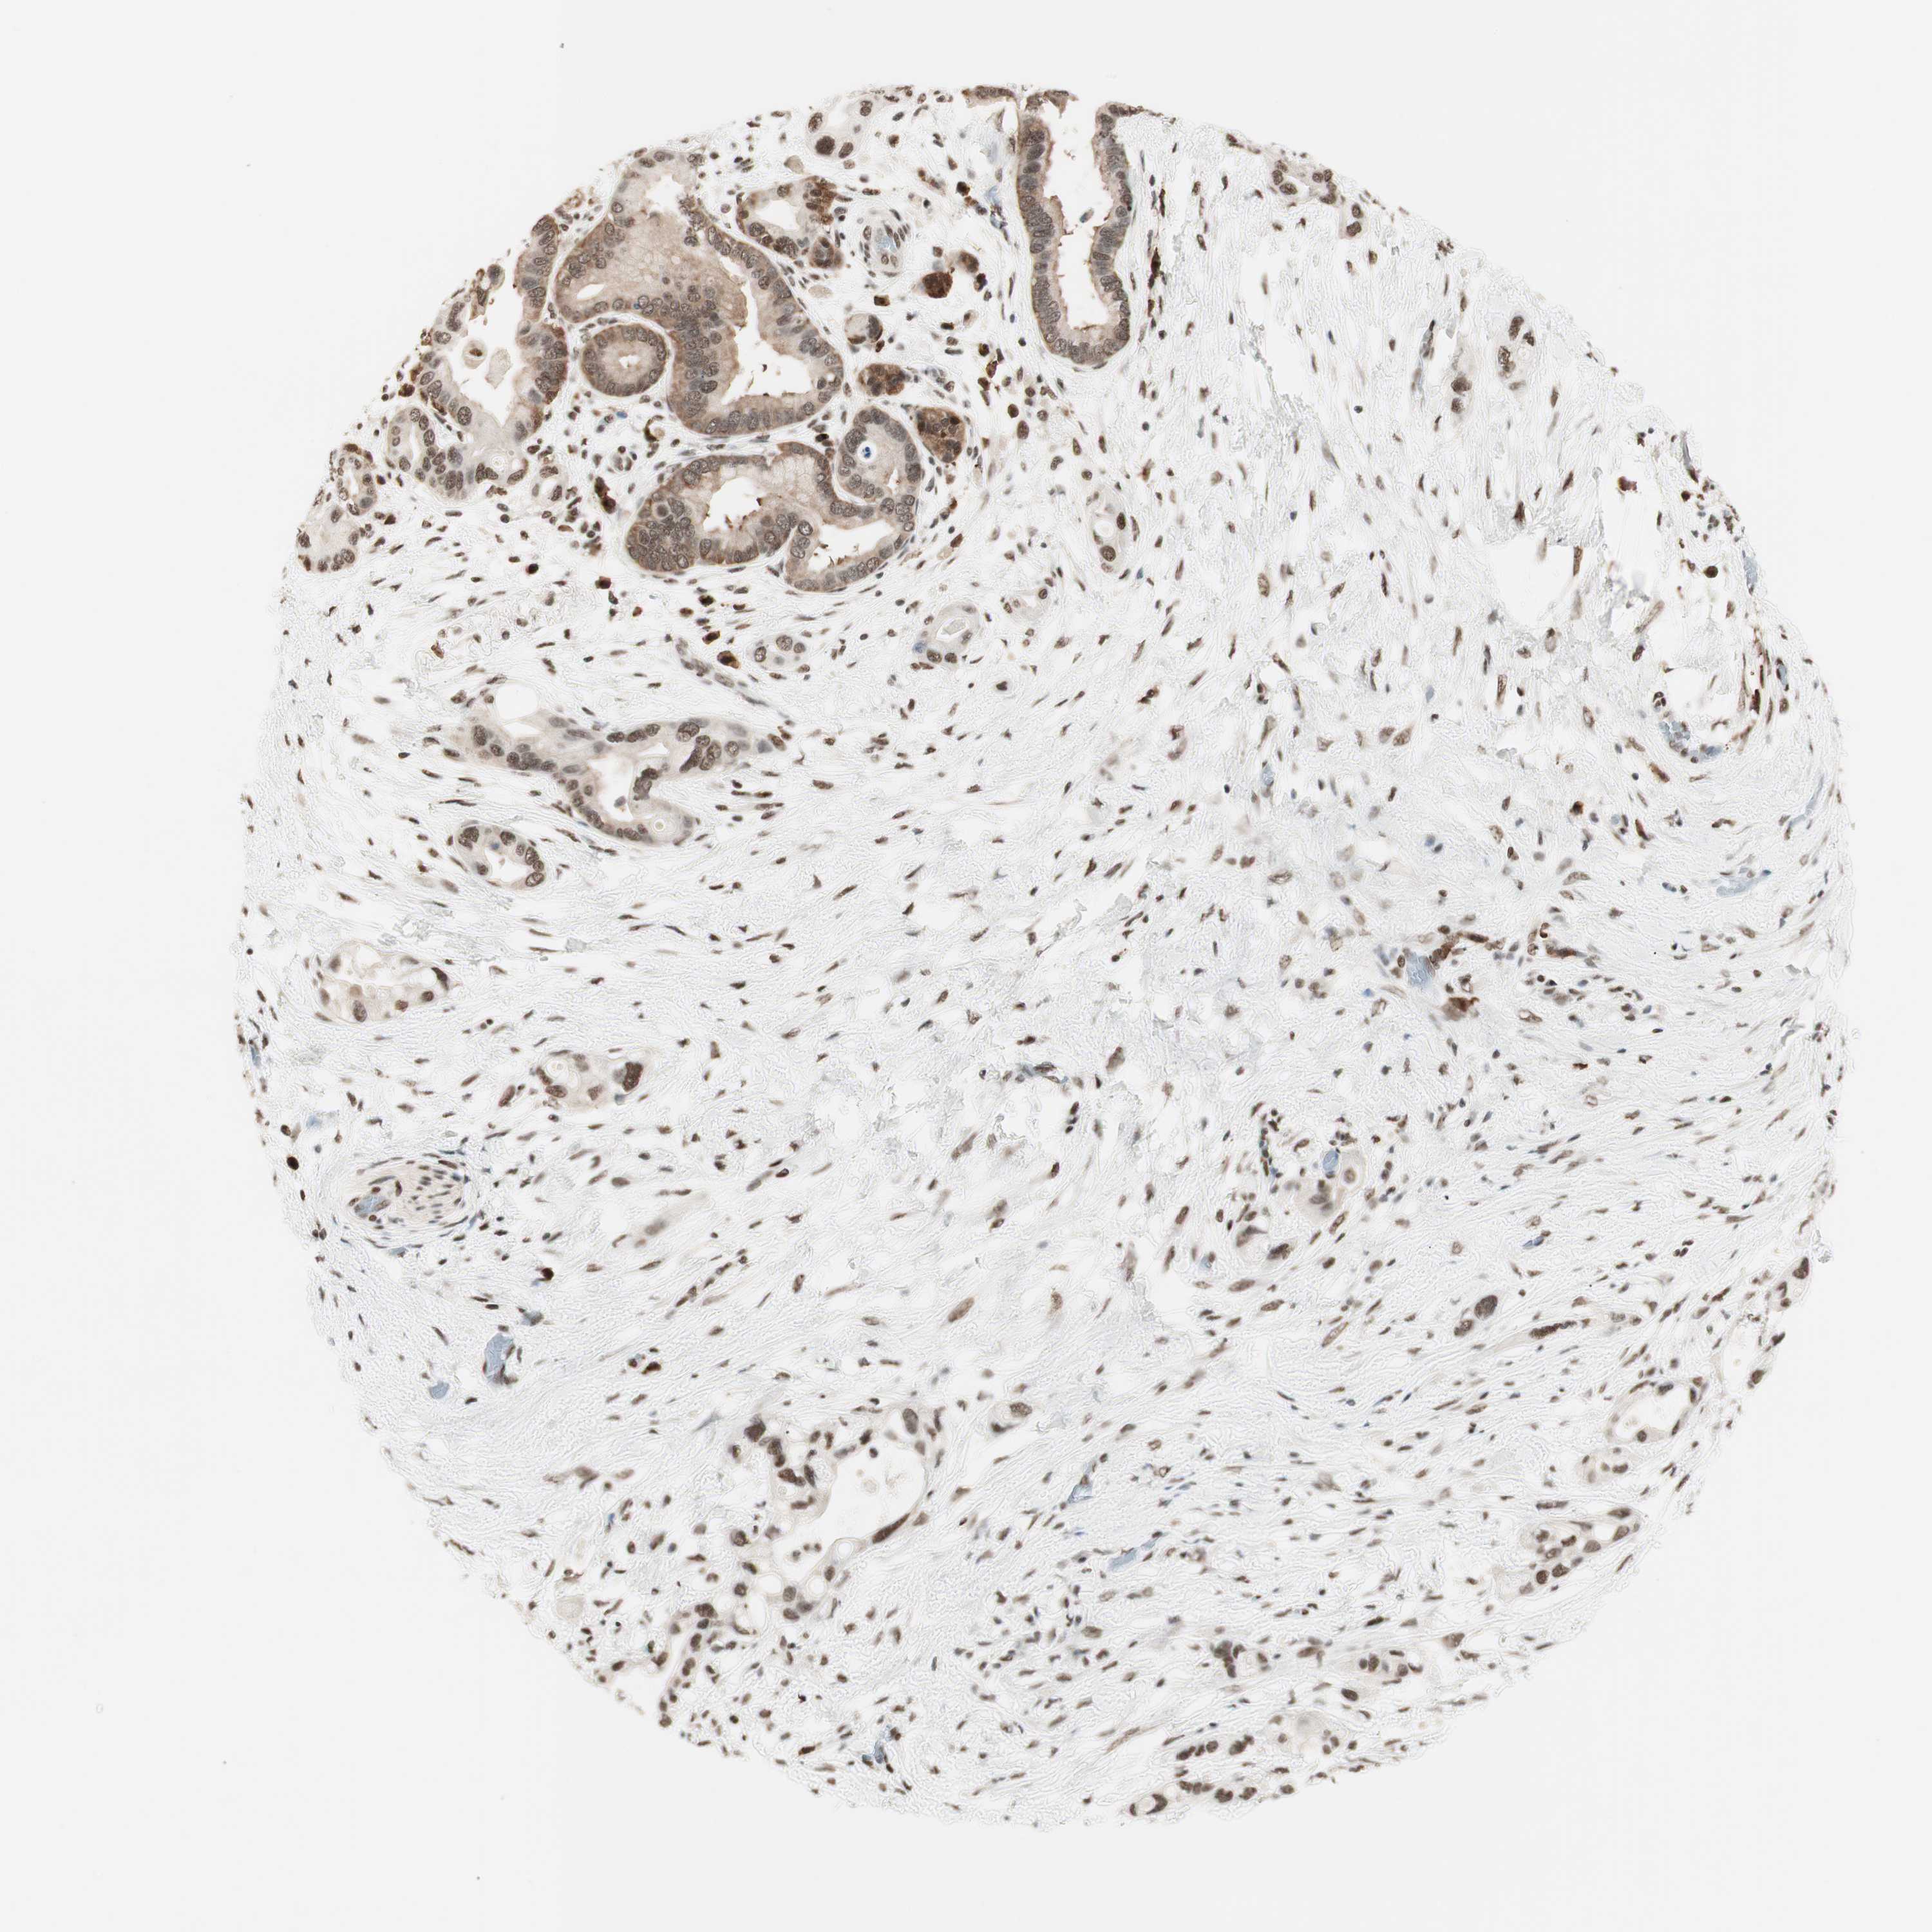

PANCREATIC CANCER - Protein expressioni

A mouse-over function shows sample information and annotation data. Click on an image to view it in a full screen mode. Samples can be filtered based on level of antibody staining by selecting one or several of the following categories: high, medium, low and not detected. The assay and annotation is described here.

Note that samples used for immunohistochemistry by the Human Protein Atlas do not correspond to samples in the TCGA dataset.

Antibody stainingi

Antibody staining in the annotated cell types in the current human tissue is reported as not detected, low, medium, or high, based on conventional immunohistochemistry profiling in selected tissues. This score is based on the combination of the staining intensity and fraction of stained cells.

Each image is clickable and will lead to virtual microscopy that enables deeper exploration of all samples and also displays staining intensity scores, fraction scores and subcellular localization as well as patient and tissue information for each sample.

Antibody HPA003916

Antibody CAB037318

Staining

High

Medium

Low

Not detected

Intensity

Strong

Moderate

Weak

Negative

Quantity

>75%

75%-25%

<25%

None

Location

Nuclear

Cytoplasmic/membranous

Cytoplasmic/membranous,nuclear

Adenocarcinoma, NOS

Adenocarcinoma, metastatic, NOS